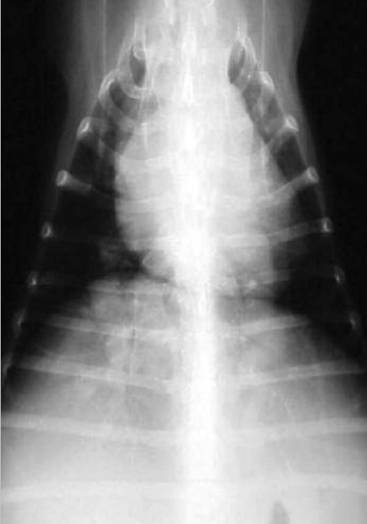

X线检测

X线不能单独用来诊断心丝虫,但是可以判断疾病的严重程度,评估心肺的实质性变化。心丝虫病X线检测可见病变包括右心室肥大(图3),肺主动脉段突出,肺主动脉密度和大小增加,动脉弯曲。背腹位X片可观察肺后叶血管尺寸。如果血管直径大于第九肋骨直径,那么就是出现异常变化。左侧位X片可以评估肺前叶动脉,正常情况下其直径不能大于伴行的静脉或最接近的第四肋骨直径的三分之一(图4)。胸部X线还可检测肺部渗出物、结节、淋巴结及胸腔积液。肺实质变化包括肺泡间隙及肺泡的病变,特别是肺后叶会比较严重。另外,还会出现肺部嗜酸性肉芽肿。X线检测的变化可能是暂时性的,一般不能诊断为活跃的感染状态。

图3 心丝虫病例背腹位X光片,可以看到右心扩张。